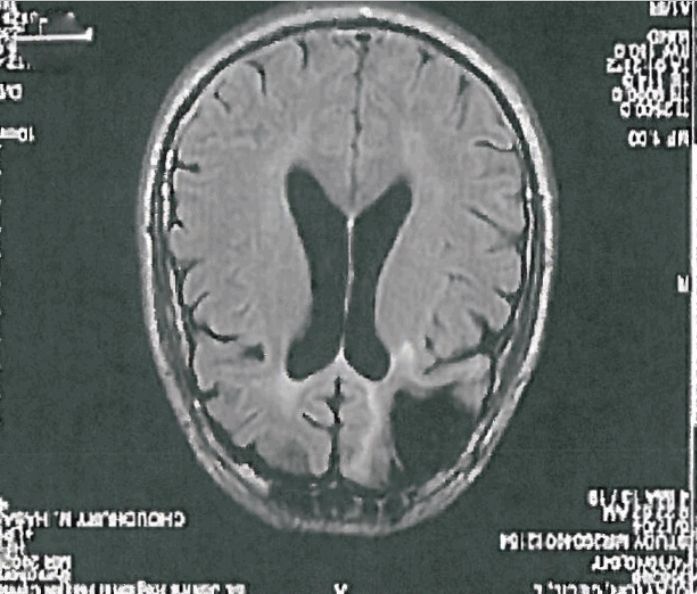

1. RT @TheAtlantic: Will Missouri execute a man with brain damage today? theatln.tc/1MIyjBl